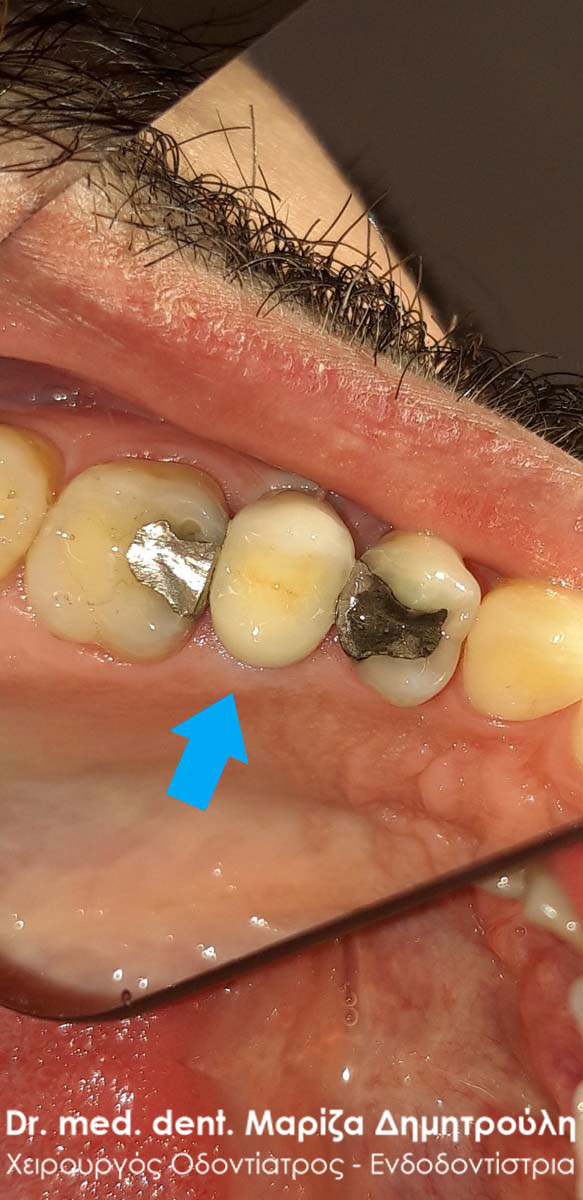

Ο ασθενής προσήλθε πρησμένος στην αριστερή πλευρά της κάτω γνάθου. Το πρόβλημα αφορούσε δύο γομφίους, από τους οποίους ο ένας ήταν ήδη απονευρωμένος και ο άλλος είχε βαθύ σφράγισμα, το οποίο έφτανε στο ύψος του νεύρου του δοντιού. Μετά την κλινική και ακτινογραφική εξέταση του δοντιού αποφασίστηκε η απονεύρωση του ενός γομφίου και η επανάληψη απονεύρωσης του άλλου γομφίου. Στο τέλος τα δύο δόντια θα προστατευτούν με θήκες δοντιών, εφόσον τα οδοντικά ελλείμματα ήταν μεγάλα.

Αρχική κλινική εικόνα του ήδη απονευρωμένου πρώτου γομφίου